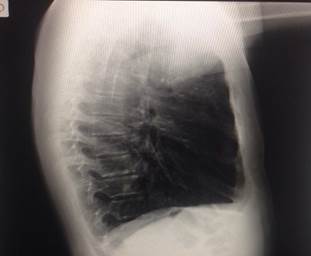

Es nuestro interés referirnos a un hombre joven suramericano de 23 años y a su problema de salud, este joven sin síntoma alguno consultó en un centro de asistencia médica de su país a un colaborador cubano; intentaba ingresar en la armada y acude para iniciar un chequeo médico necesario. El examen físico cardiocirculatorio fue inusual al igual que sus estudios imaginológicos donde aparecen y sorprenden por lo inesperado los hallazgos que más adelante se expondrán. Al final el paciente no necesitó de ningún tratamiento médico específico, solo recibió información detallada de la malformación congénita cardíaca y las medidas de prevención ante cualquier emergencia por esta anomalía cuyo nombre se conoce como ectopia cordisabdominal (ECA), no podría ingresar en la fuerza armada. Se le explica por qué no aparece la silueta cardiaca y vascular al rayo x (Rx) de tórax postero anterior (PA) (Figura 1).

Ni en la vista lateral (L) (Figura 2).